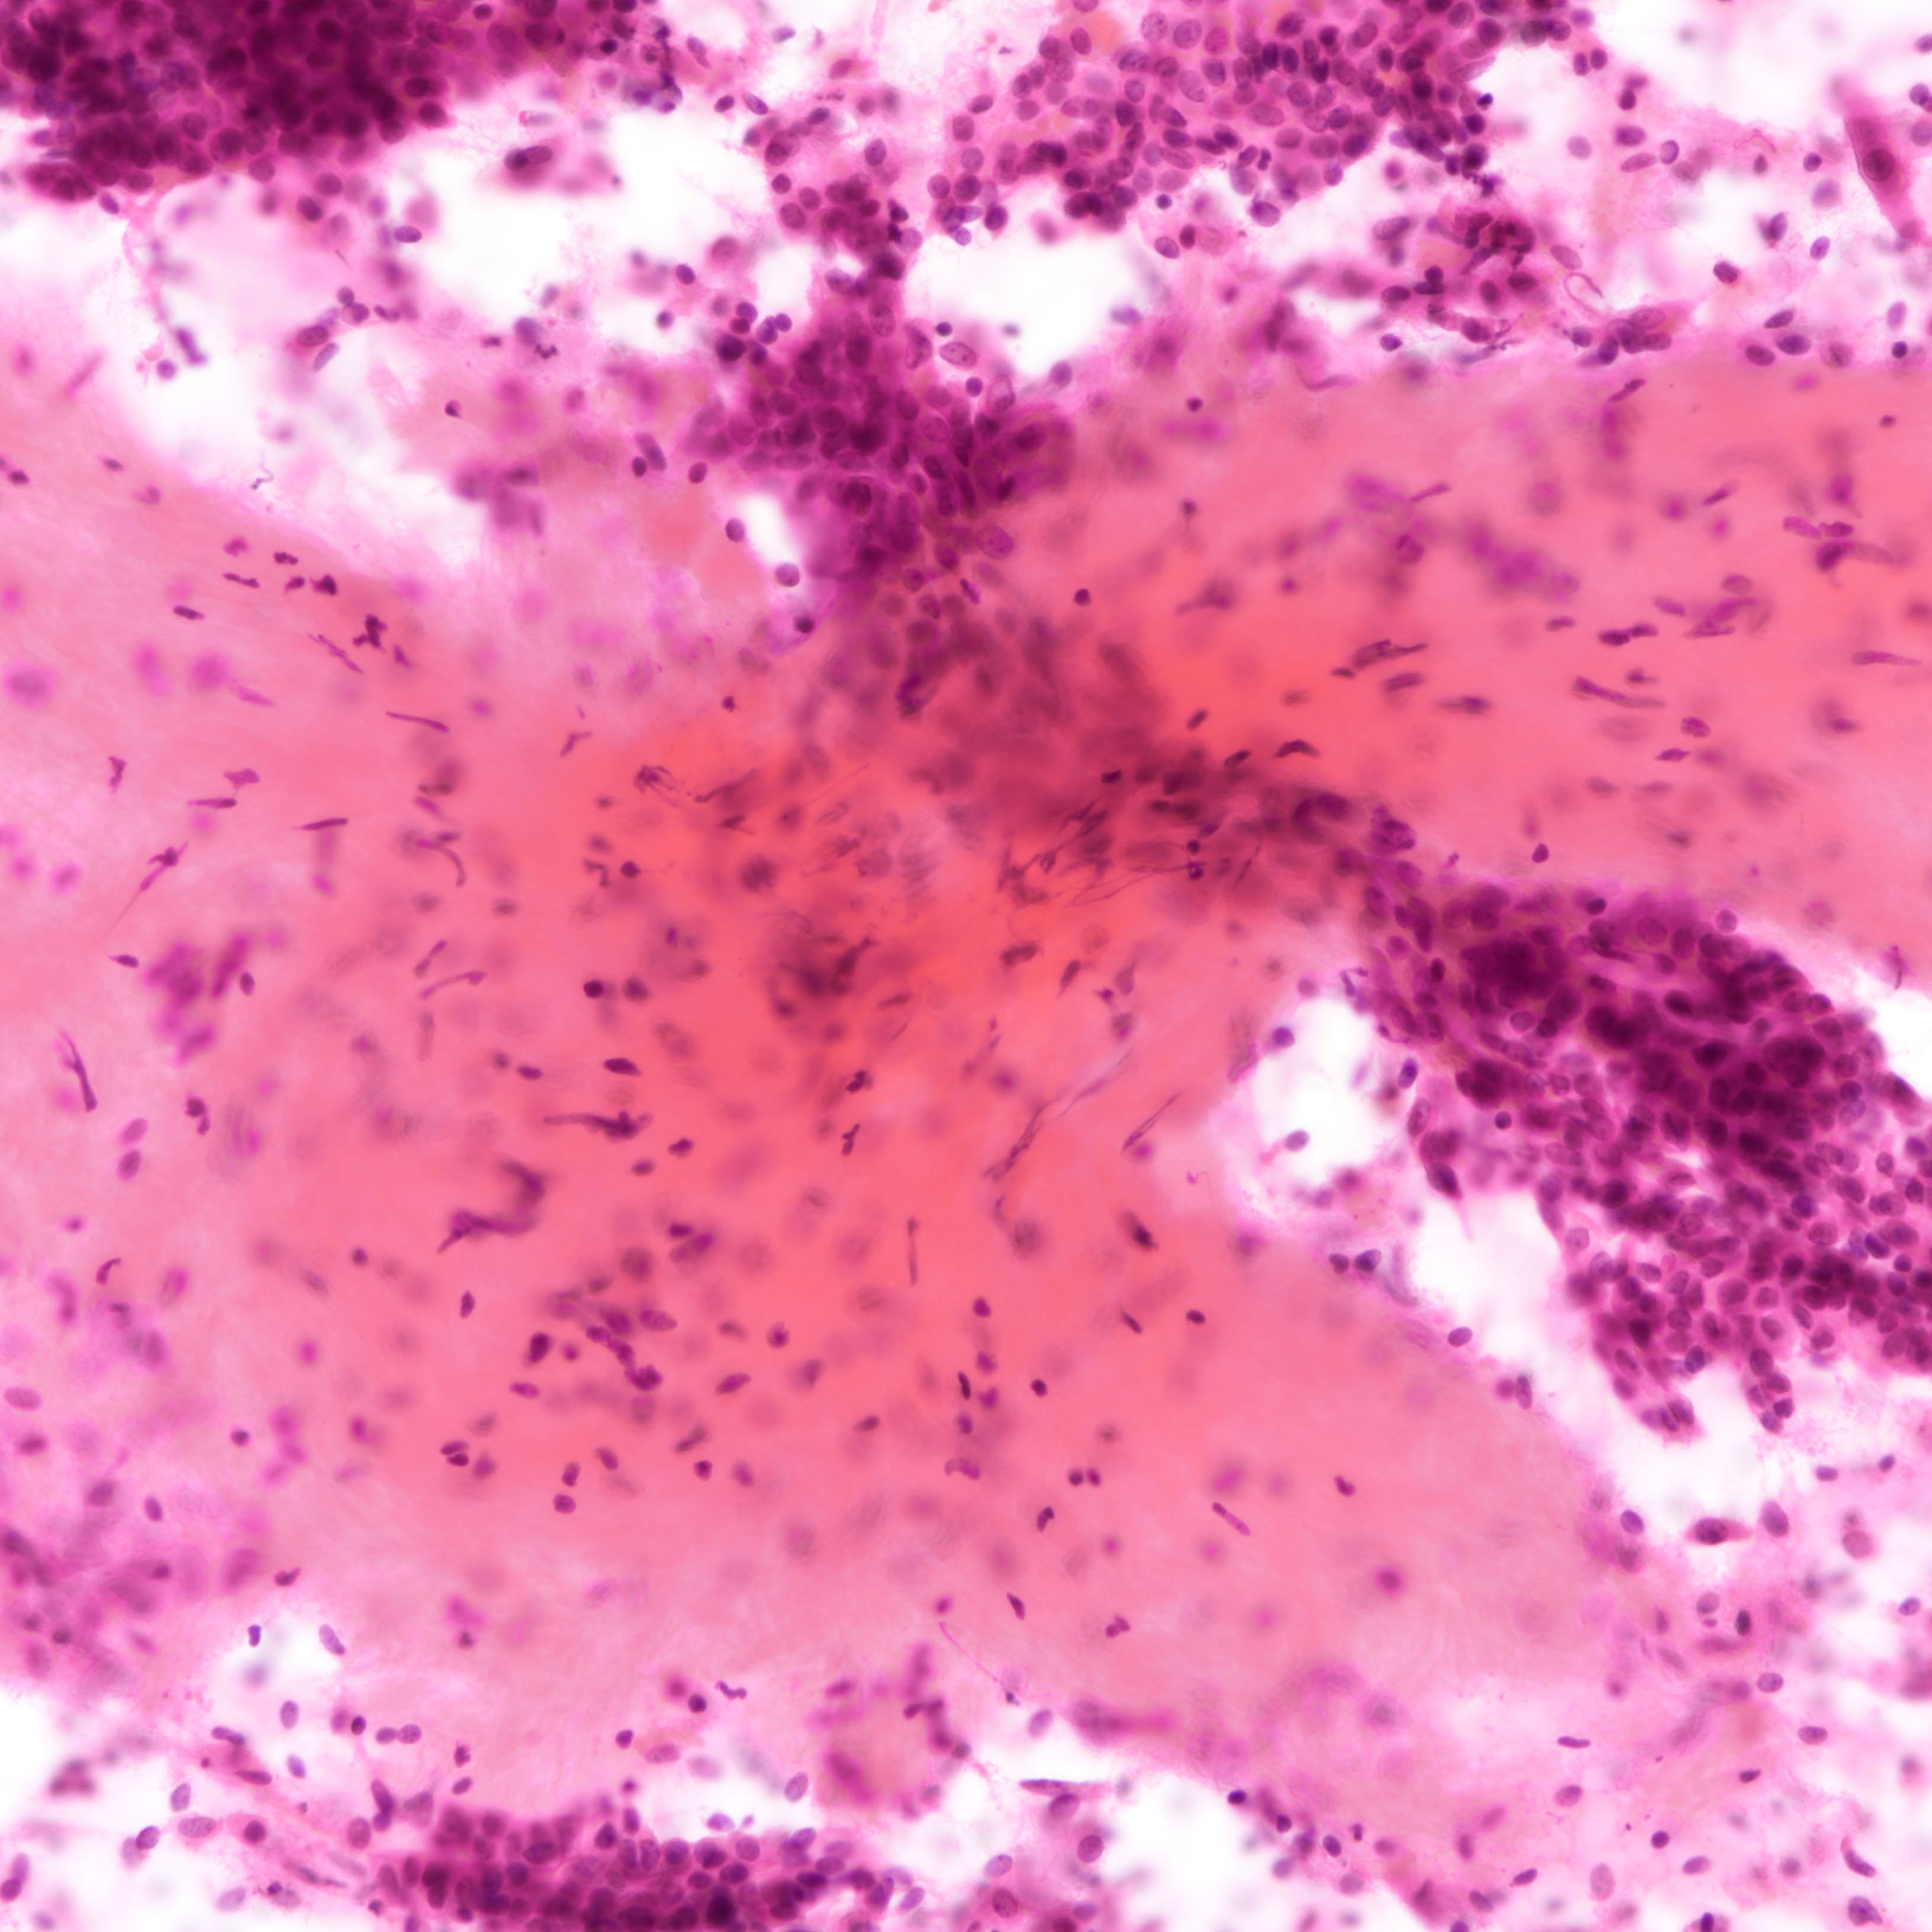

Cytology description

- Fibromyxoid stromal clumps

- Reduced epithelial stromal ratio compared with fibroadenomas

- Higher nuclear atypia and cellularity in phyllodes tumor of higher grades

- Large wavy and folded epithelial clusters

- Usually exhibits benign cytomorphology

- Occasionally, hyperplastic changes with enlarged and vesicular nuclei and small visible nucleoli may be seen

- Fibroblastic pavements

- Increased atypia in dispersed cells in phyllodes tumor of higher grades (Cancer Cytopathol 2010;118:33)

- Multinucleated tumor cells and marked stromal anaplasia reported in malignant phyllodes tumor (Cancer Cytopathol 2010;118:33)

Cytology images

Contributed by Joshua J.X. Li, M.B.Ch.B. and Gary M. Tse, M.B.B.S.

Malignant phyllodes tumor